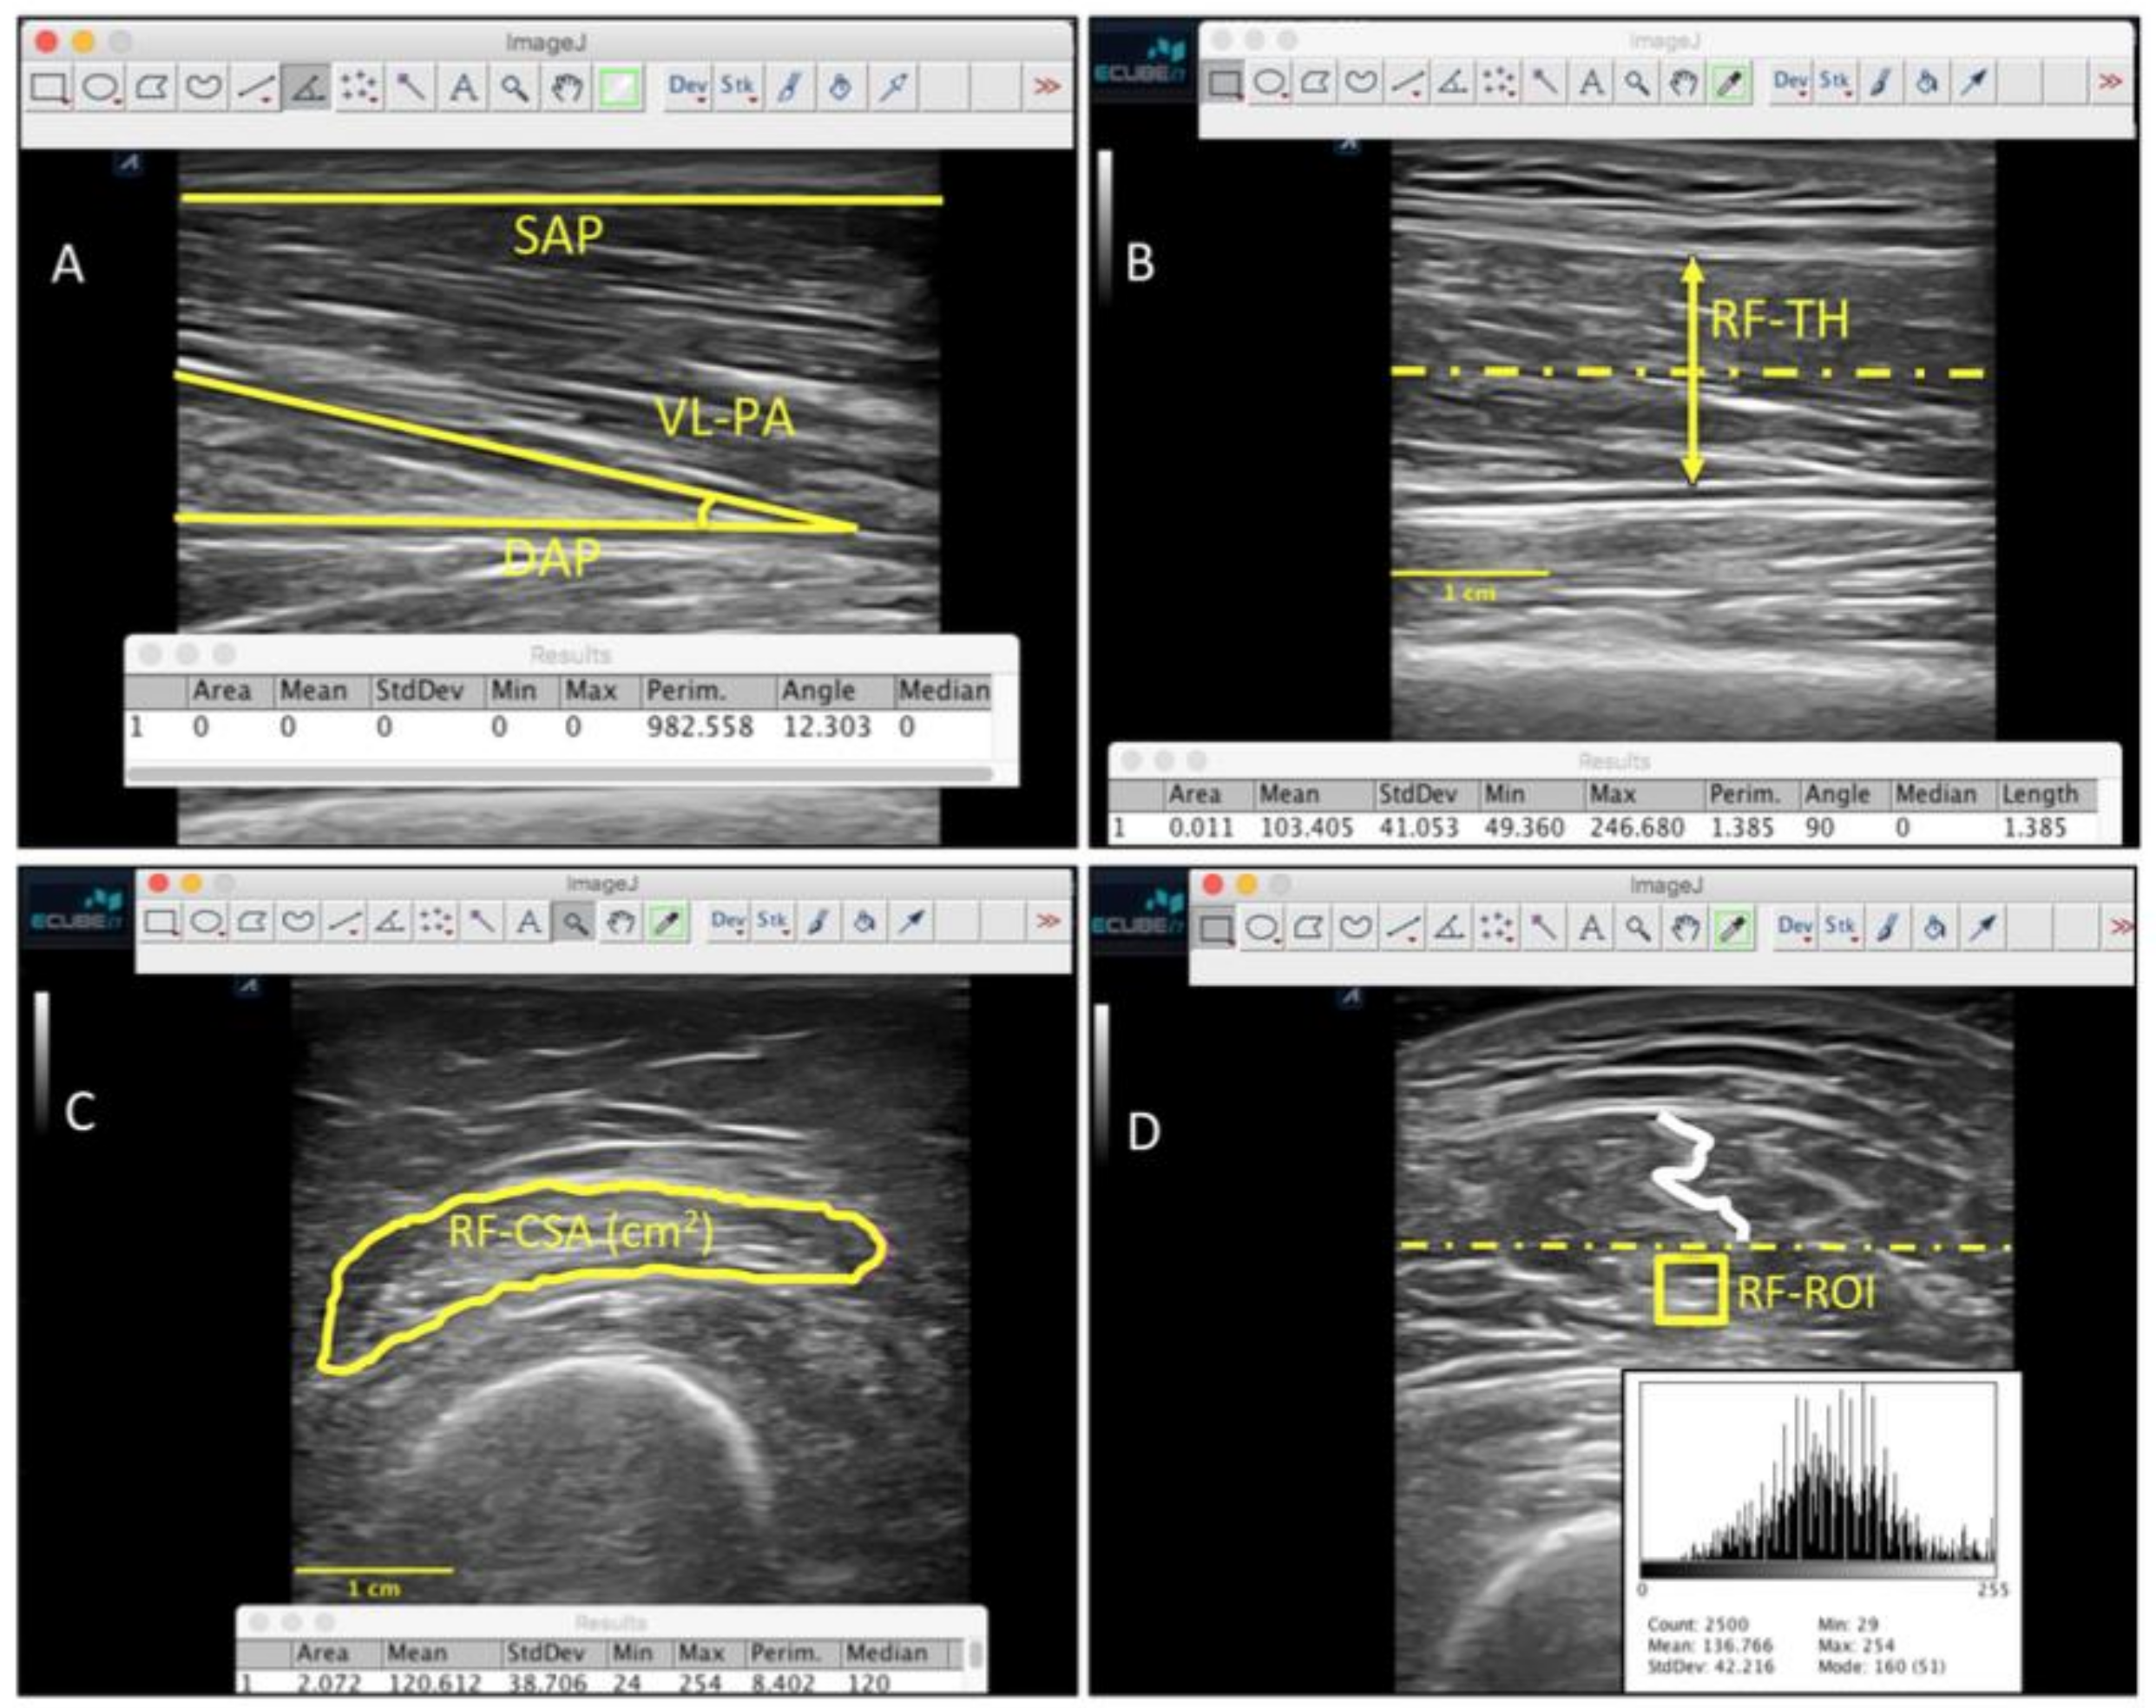

2.9. Ultrasound Imaging Evaluation